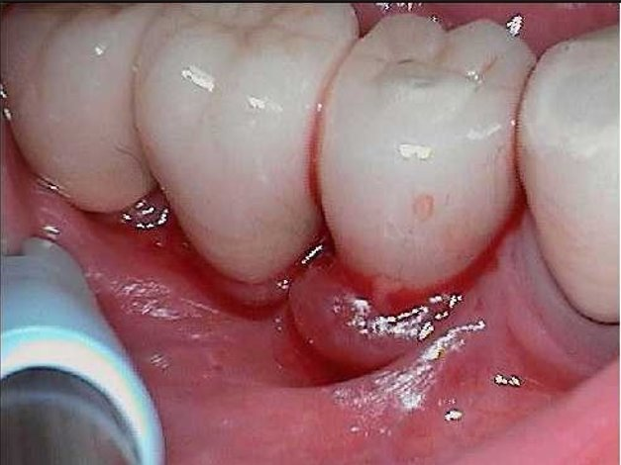

April 16, 2024: 99-year-old patient with peri-implantits​ exhibited suppuration and bleeding on #29

​PerioProtect Trays delivered 4/26/24​ at maintenance appointment after patient declined periodontal surgery.

Patient Returns for Visit on August, 19, 2024 (4 months later). Impacted food was removed on the lingual margin. Note the tissue improvement on the buccal margin.